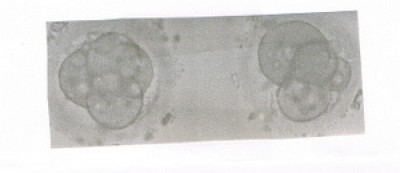

Ewi alle befruchtet, besser gehts ja gar nicht

. Na dann bekommst du jetzt noch

das du schöne Blastos wiederbekommst. Deine Bedenken kann ich verstehen, ist bestimmt kein Zuckerschlecken mit Zwillis ss zu sein.